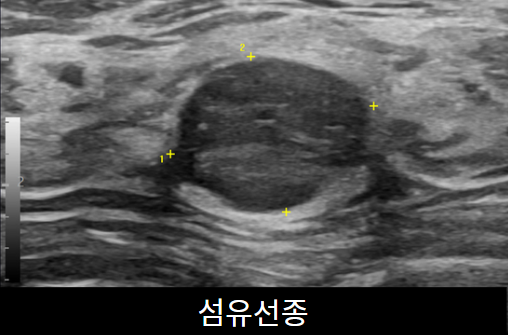

유방초음파

유방초음파 검사를 통해 유방낭종,염증, 종양을 진단할 수 있습니다. 유방촬영술과 같이 진행하는 것이 이 정확한 진단을 위해 필요합니다. 약 10~15분 소요됩니다.